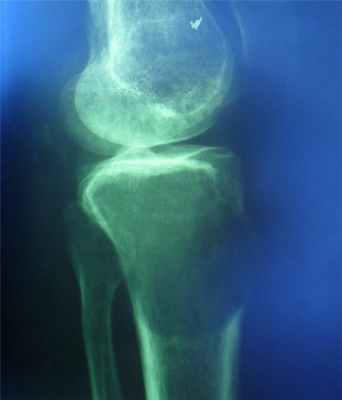

(Слева) Рентгенография в ПЗ проекции: типичный крупный костный островок. Равномерный участок склероза с краями в виде щетки, которые переходят в нормальную кость. Четкий склерозированный край отсутствует.

б) Визуализация:

• Рентгенография в большинстве случаев позволяет установить правильный диагноз:

о Гомогенный участок уплотнения, угасающего к периферии с переходом в нормальную трабекулярную структуру

о Края участка имеют вид щетки; могут быть звездчатыми

о Ассоциированный отек костного мозга или кортикальная деструкция отсутствуют

о Поражение может быть полиоссальным